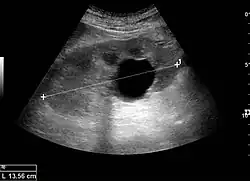

Простая почечная киста

Простые почечные кисты тонкие, круглые мешочки заполнены прозрачной жидкостью, и они не являются злокачественными.